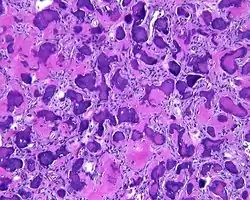

By microscopic evaluation, the tumors are composed of a variably cellular stroma make up of spindled to stellate fibroblast-like cells. Within this stroma, are numerous small, rounded, mineralized collagenous ossicles and immature osteoid. Many times the curved-shaped bone fragments have a collagenous rim around them. Ossicles may fuse to form much large mineralizations. Cementum-like psammomatous bodies (cementicles) may also be present. Osteoblastic rimming is not uncommon. Occasionally, giant cells and even mitoses are seen.[1][3]